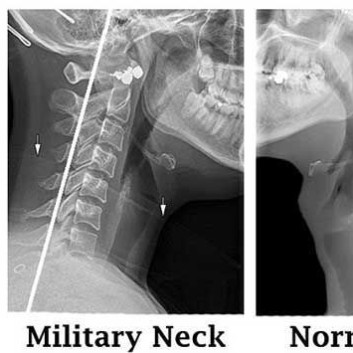

일자목(거북목)이란?

목뼈는 옆에서 보았을 때 C자 형태로 정상적인 커브를 나타내고 있어야 하는데 일자 형태의 수직으로 변형된 상태를 일자목 또는 거북목이라고 합니다.